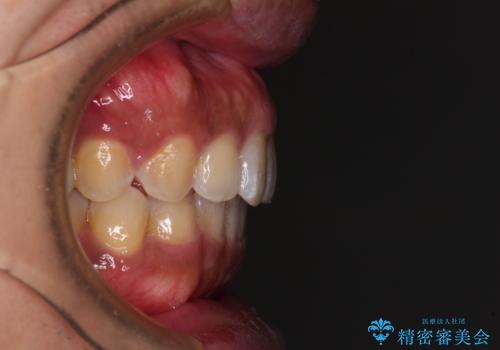

破折して抜歯が必要となった歯の後ろの歯は、根管治療が必要な状態であったので、根管治療を行い、矯正治療後にインプラント部の補綴治療と同時にセラミッククラウンを装着しました。

矯正治療以外に費用負担がかかることになりましたが、気になるところ全てを処置することができ、患者様には大変満足していただきました。